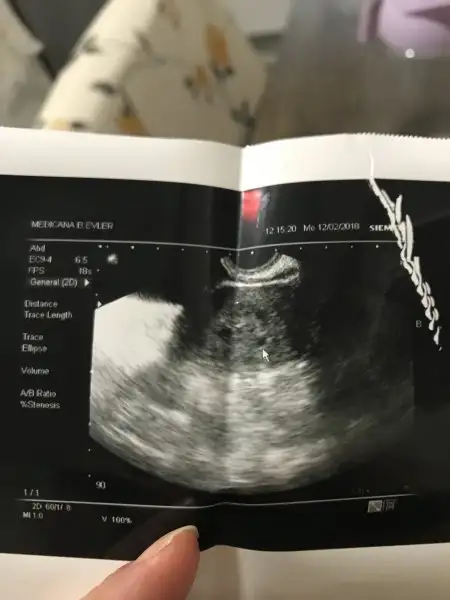

Benim de bugün kese göründü çok şükür karından göründü alttan da bakıldı adete göre 5+6 ama resimde 4+6 yazıyor transferin 18.günü bugün anlamadım bir de benim transfer geç oldu 22.gündü

Hayırlı olsın kağıdın neresinde yazıyor acaba hafta günü benim doktorum gün ile ilgili bişey demedi vajinal muayene ile keseyi gördü o kadar

• 371C9848-8186-41CD-9E07-D0AB4D288302.webp

371C9848-8186-41CD-9E07-D0AB4D288302.webp

12,8 KB · Görüntüleme: 84